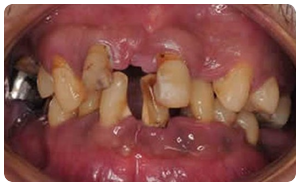

症例①

【初診時】

:年齢:30代前半

:状態:軽度歯周炎、喫煙あり、基礎疾患無し

:治療:ブラッシング指導、禁煙指導、スケーリング、ルートプレーニング、安定してからは2ヶ月ごとのメンテナンス(喫煙なし)